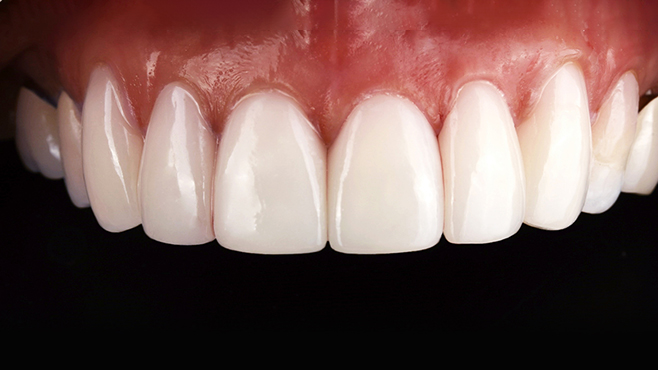

맞는 건 괜찮은데… 충치는 못 참겠습니다|20대 격투기 선수 치과 방문기